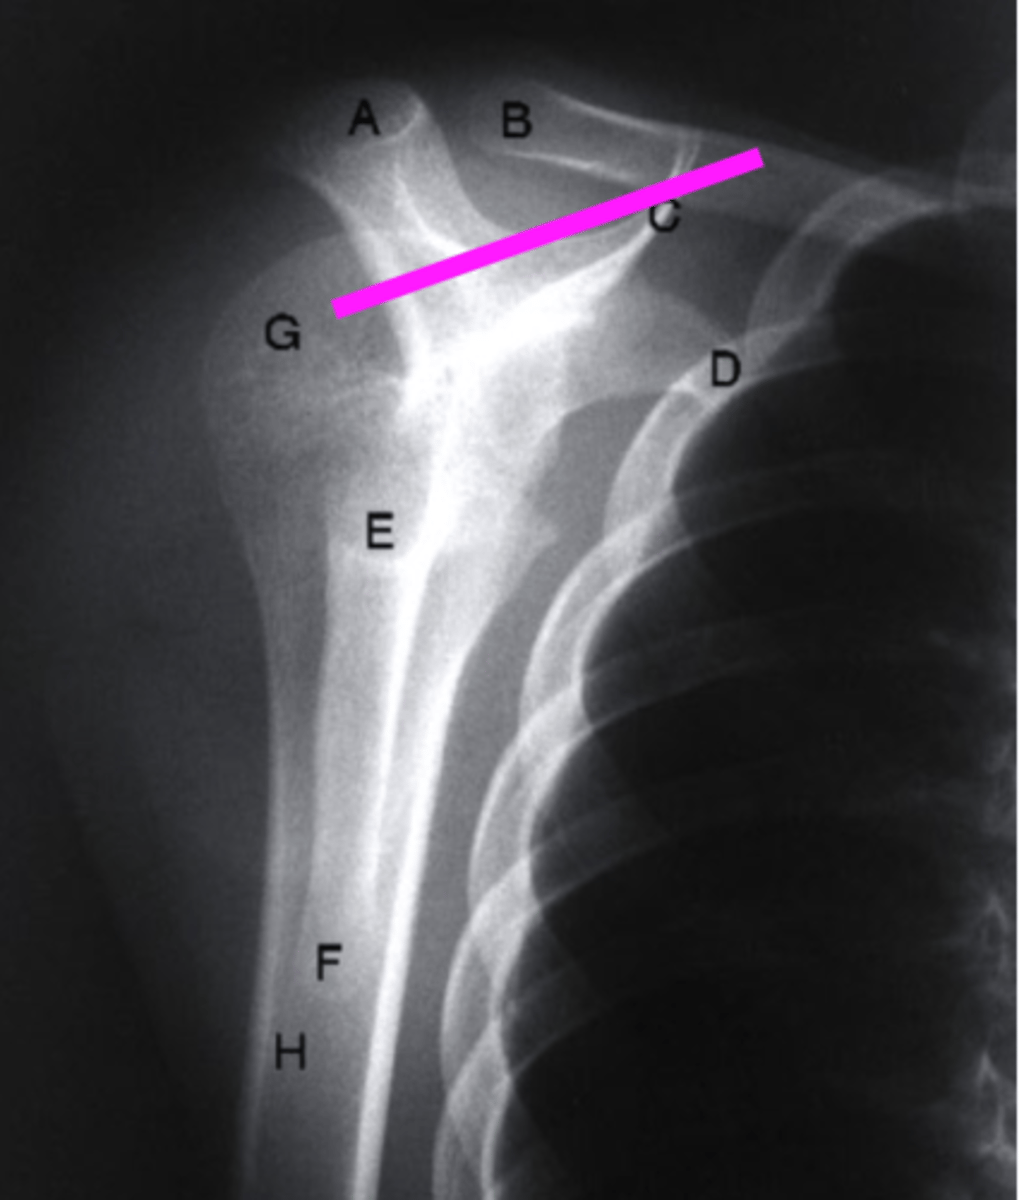

AP + IR

what view is this?

clavicle

what does the pink line point to?

spine of scapula

coracoid process

glenoid fossa of scapula

AC joint

acromion

Humeral Head

lesser tubercle